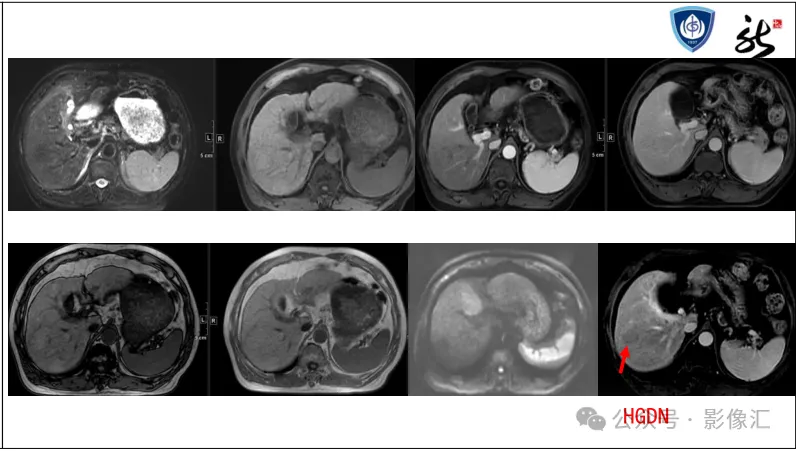

>【精品课件】如何正确判读肝胆特异性对比剂增强图像?

肝胆特异性对比剂增强肝胆图像判读方法与策略,课件来源于网络,作者复旦大学附属中山医院放射科饶圣祥教授。